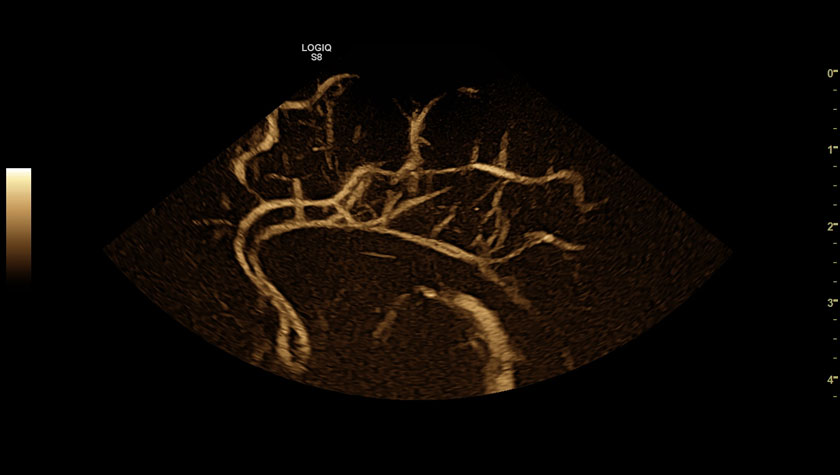

Мозг новорожденного в режиме B-FLOW, датчик 10C-D

- Режим B-flow – оценивает гемодинамику во всех типах сосудов: от крупных кровеносных сосудов, например, сонной артерии, до мелких сосудов паренхиматозных органов.

- B-Flow — Технология для высокоточной визуализации гемодинамики;

- 3D — трехмерное сканирование в статическом режиме

- 4D — трехмерное сканирование в реальном масштабе времени